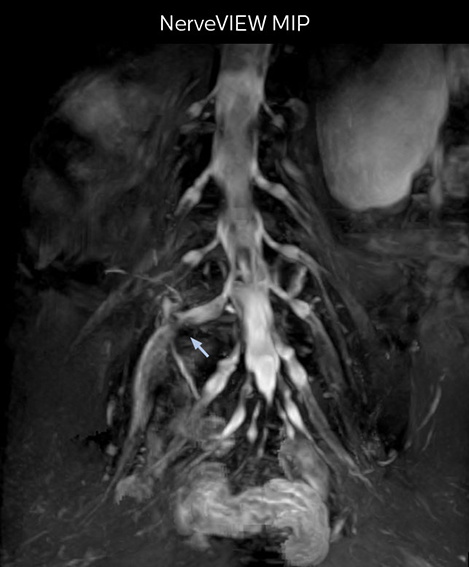

At Northern Fukushima Medical Center in Japan, excellent MRI visualization of nerves helps support confident diagnoses and informs surgical treatment decisions for patients with lower limb symptoms. MRI technologist Tanji and orthopedic surgeon Dr. Yabuki share how direct nerve visualization with the 3D NerveVIEW method adds information when diagnosing atypical herniations. The additional insights changed their way of working and benefit their patient care, as illustrated by some clinical examples.

Northern Fukushima Medical Center (NFMC) Imaging Center uses the 3D NerveVIEW sequence for performing MR neurography, particularly in patients with pain and weakness in the lower limb. “It is included in about 20% of the approximately 150 lumbar spine MRI exams each month at NFMC, and can help us to determine if structures are impinging on the nerves,” says Hajime Tanji, RT, MRI technologist at NFMC.

“In such case, we would then browse through axial T2-weighted MR images slice by slice and mentally reconstruct the actual situation based on both radiculography and MRI. Fortunately, NerveVIEW can now very well show nerve courses and presence of nerve compression or edema in one single image series.” “We have often seen NerveVIEW directly depict details of the nerve compression that were not observed by radiculography. Therefore, we think that with NerveVIEW we can reduce the number of invasive examinations, especially for some patients with lumbar plexus symptoms.”

“NerveVIEW is really useful for those cases where a nerve disorder is strongly suspected based on the clinical examination but our regular MRI images do not show any findings. These atypical herniations and spinal canal stenosis, occurring in 5% to 15% of the total lumbar herniation/stenosis cases are our main target when using NerveVIEW,” says Dr. Yabuki.

“NerveVIEW can clearly show nerve courses and presence of nerve compression. However, when multiple abnormalities are seen, it can still be hard to determine which nerve is causing the symptoms,” says Dr. Yabuki. “In our experience so far, we see abnormal findings on NerveVIEW in about 70% of elderly patients. As the pain is usually caused by only one nerve, we thus need to find the exact corresponding nerve.” “With a nerve root block, the patient's pain is improved by infiltration of local anesthesia directly around the nerve root considered to be responsible. Knowing such nerve root block findings prior to image interpretation, helps to easily recognize abnormal findings on NerveVIEW as well. In other words, without a priori knowledge, based on symptoms and/or nerve root block findings, we must be aware of the possibility of overdiagnosis.”

The addition of the nerve-selective NerveVIEW sequence to its spine MRI protocol has given NFMC competitive advantages, according to Tanji. “Since we started including NerveVIEW routinely, the demand for lumbar spine MRI examinations has increased, especially for pre-surgical planning purposes and for patients with chronic lower extremity symptoms,” he says. “Moreover, because no other hospitals in our region are doing nerve plexus imaging yet, we often receive referrals for MR neurography studies from other hospitals even if they have an MRI scanner. Some requests come from as far as 100 km away. NerveVIEW definitely provides us a competitive advantage.” “Based on our experience, we can certainly recommend NerveVIEW to other centers,” Dr. Yabuki adds. “The sequence opens up many possibilities to facilitate the diagnosis of lower extremity pain and to inform our decision-making regarding therapy and surgery.”